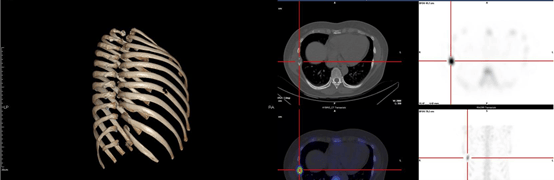

患者女性,52岁,因“右侧胸壁疼痛2周”就诊。患者2025年8月中旬开始无明显诱因下出现右侧胸壁疼痛,表现为右侧胸壁持续性钝痛,需口服NSAID类止痛药才能缓解,病程中,患者否认胸闷、气急、刺激性咳嗽、咳痰、咯血、发热等不适,患者遂于外院就诊,2025.08.28外院予以行胸部平扫CT检查提示右侧第7肋骨肿物伴骨质破坏,2025.08.30予以进一步行PET/CT检查提示右侧第7肋骨肿物,大小约2.0*3.0cm,伴周围骨质破坏,FDG代谢增高,SUVmax=8.6,考虑恶性病变可能,倾向原发,未见其他部位肿瘤性病变。后患者于我院就诊,入院予以肋骨三维CT重建(2025.09.02)提示右侧第7肋骨肿物伴病理性骨折,骨扫描(2025.09.03)提示右侧第7侧肋可见局部骨质密度减低伴骨质破坏,考虑恶性病变,余未见其他骨病变,头颅增强MRI检查未见颅内病变。

朗格汉斯细胞组织细胞增生症的影像学诊断首选PET/CT,尤其是对于骨骼病变的检出要优于CT和MRI,表现为高摄取的溶骨性改变。中枢神经系统病变首选MRI检查,肺部病变首选胸部CT。但LCH的确诊主要靠病理诊断,其主要病理形态学特点为:瘤细胞呈片、巢状分布,胞质丰富、淡染,细胞核呈肾形、咖啡豆样、有核沟,背景常伴有淋巴细胞、嗜酸性粒细胞、组织细胞、纤维母细胞及多核巨细胞。免疫组化特点为CD1a、Langerin(CD207)及S-100蛋白阳性,其中CD1a和Langerin的灵敏度及特异度均较高,是确诊LCH所必需的[3]。此外,超过50%的患者合并有BRAF-V600E的突变[4]。

因此,基于现有的少量研究及临床实践,对于肋骨LCH的患者,应进行充分的术前评估,包括全身PET/CT及头颅MRI评估基线疾病负荷,对于单发的肋骨LCH的患者,手术切除是可治愈的治疗策略,对于多病灶的患者,手术切除联合全身治疗也可获得良好的临床疗效,但仍需要大规模的前瞻性研究进行验证。